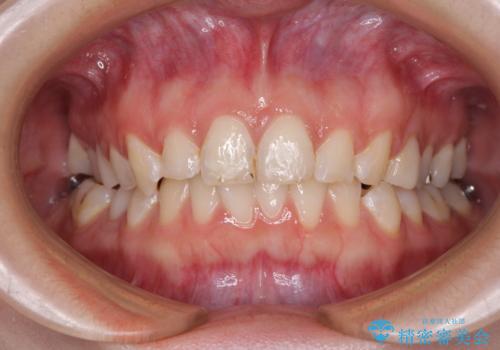

インビザラインでの矯正治療を希望されていましたが、奥歯の咬み合わせがインビザライン単独では改善困難と判断されたので、補助装置を併用することとしました。

まずは裏側の装置やワイヤー矯正を用いて歯列幅の狭い上顎を側方に拡大しつつ全体を後方に移動させ、その後インビザラインにて歯列を整えることとしました。

奥歯の咬み合わせの改善は、インビザライン単独では達成しきれないことがあるため、ワイヤー矯正などの補助装置を併用する場合があります。

インビザライン単独の場合と比べ、治療結果は大きく異なります。